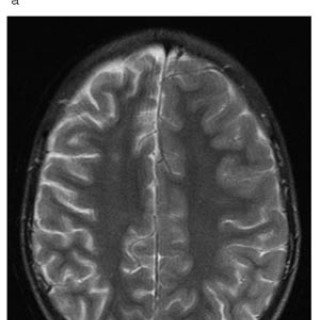

En 23 år gammel førstegangsgravid kvinne som fra tidligere stort sett var frisk, ble innlagt i lokalsykehus ved svangerskapslengde 22 uker + 2 dager, med en seks dagers sykehistorie med generell sykdomsfølelse, feber opptil 40 °C, kvalme, oppkast og anoreksi. I tillegg hadde hun fått økende ansiktsødemer, korsryggssmerter, hodepine og synsforstyrrelser. Svangerskapet hadde vært ukomplisert frem til det aktuelle. Hun var normotensiv. Blodprøvene viste kreatinin 236 µmol/l, karbamid 13 mmol/l, urat 410 µmol/l, leukocytter 15,0 · 10⁹/l, CRP 106 mg/l og trombocytter 86 · 10⁹/l. Leverprøvene var...